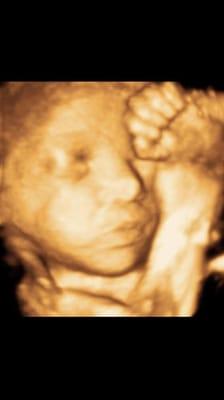

Seacoast Birth & Family Connection formed in 2015 when MAC Photography, Diagnostic Ultrasound Suite, Boston Baby Beginnings, and Bumps and Babes nutrition and lactations coach joined forces. Now in 2016 we are expanding our location to make space for other prenatal and family businesses to join our team.

Your local one stop connection to leading Seacoast experts that will help you create your ideal pregnancy, birth and parenting experience. Seacoast Birth & Family Connection is a group of professionals providing support and services for new and expectant parents. Each member provides a different service within the pregnancy and parenting industry. We have helped thousands of local families savor the precious moments of their experience.